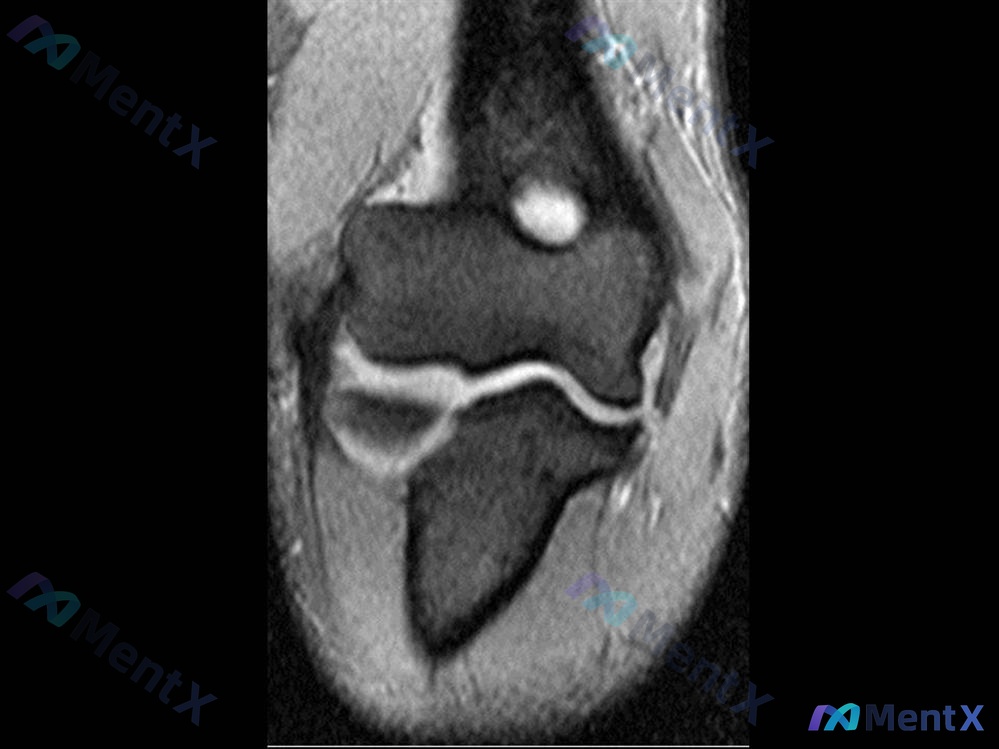

病例资料整理 患者信息:19 岁男性,大学棒球投手。 主诉:右肘反复疼痛 4 个月。 现病史: - 初次发作于投球后 4 个月前。 - 曾接受保守治疗(休息、前臂强化练习)。 - 现投掷间歇训练中疼痛复发。 影像学检查(MRI 冠状位 T2): - 关节腔内可见明显积液信号。 - 肱骨远端与尺骨/桡...